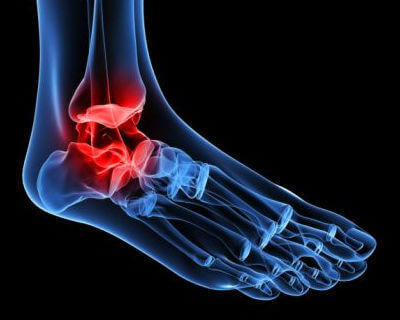

Hoe ontstaat osteoartritis van de enkels?

Toenemende slijtage van het kraakbeen in het enkelgewricht is de oorzaak van dit type osteoartritis. Als we ouder worden, is het heel normaal dat de enkels stijf worden en misvormingen zich ontwikkelen.

Klassieke botsporen kunnen ook optreden. Die maken de aandoening nog pijnlijker en beperken je nog meer in je bewegingen.